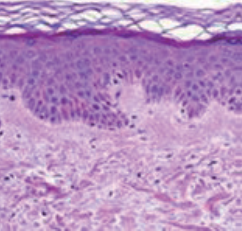

3. 피부내부조직상태

정상피부

손습진조직